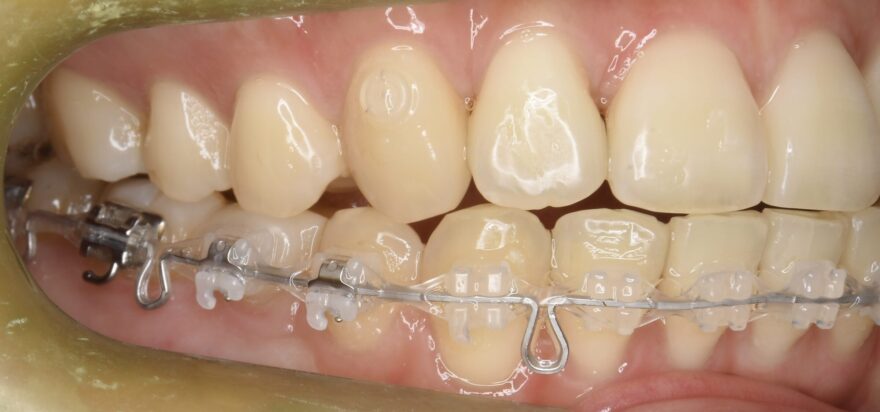

治療中の口腔内写真

上顎は裏側に矯正装置が付いています。

口蓋に2本の歯科矯正用アンカースクリューが埋め込まれ、裏側の矯正装置とゴムで繋がっていることがわかります。